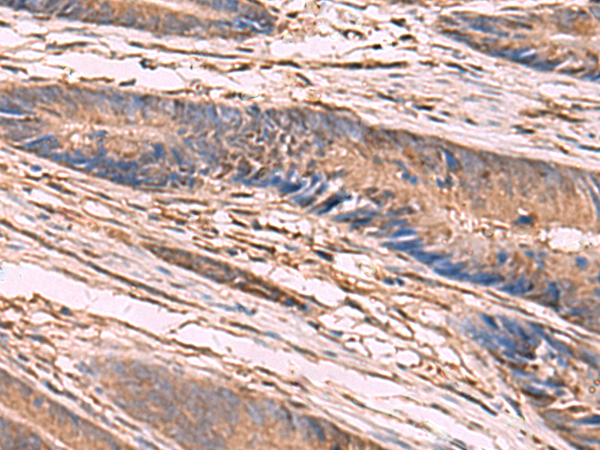

ELISA, WB, IHC |

IHC positive control: |

Human liver cancer and Human colorectal cancer |

IHC Recommend dilution: |

50-300 |